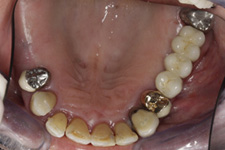

Částečně ozubená čelist

V případě chybění většího počtu zubů v postranních úsecích čelistí je možné ošetření pomocí implantátů, které nahradí ošetření pomocí snímacích náhrad kotvených na zbývajících zubech nebo patře.

Podmínkou je opět dostatečné množství kosti.

Protetické řešení může být pomocí můstku, který je kotvený na implantátech nebo pomocí jednotlivých korunek na implantátech.

V zásadě je možné do těchto můstků zařadit i přirozené zuby, zejména pokud je potřeba tyto zuby ošetřit proteticky – korunkami. Korunky nebo můstky mohou být na implantáty nacementovány nebo přišroubovány.

Zdravé zuby zůstanou zachovány a přitom náhrady jsou pevné, jako na vlastních zubech